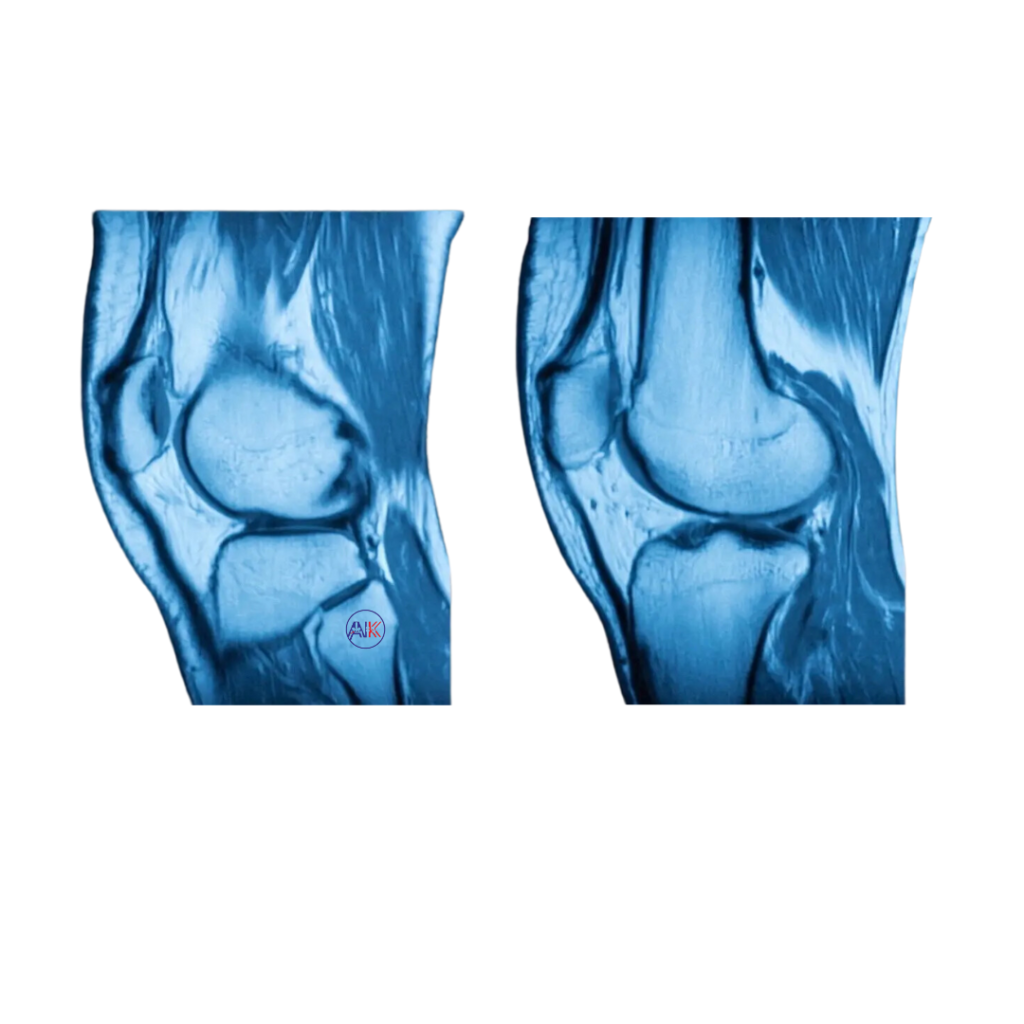

ACL TEAR, RUPTURE, INSTABILITY, OR INJURY

Injuries to the anterior cruciate ligament (ACL) in the knee can lead to tears, ruptures, or instability, often causing pain and affecting knee function.

TEARS OR INJURIES TO THE MENISCUS

These injuries can involve the C-shaped cartilaginous structures in the knee (menisci), potentially leading to pain, swelling, and limited knee function.

CARTILAGE INJURIES, DEFECTS, OR CHONDRAL LESIONS

These issues may involve damage to the articular cartilage, resulting in cartilage injuries, defects, or chondral lesions. They often lead to pain and joint dysfunction.